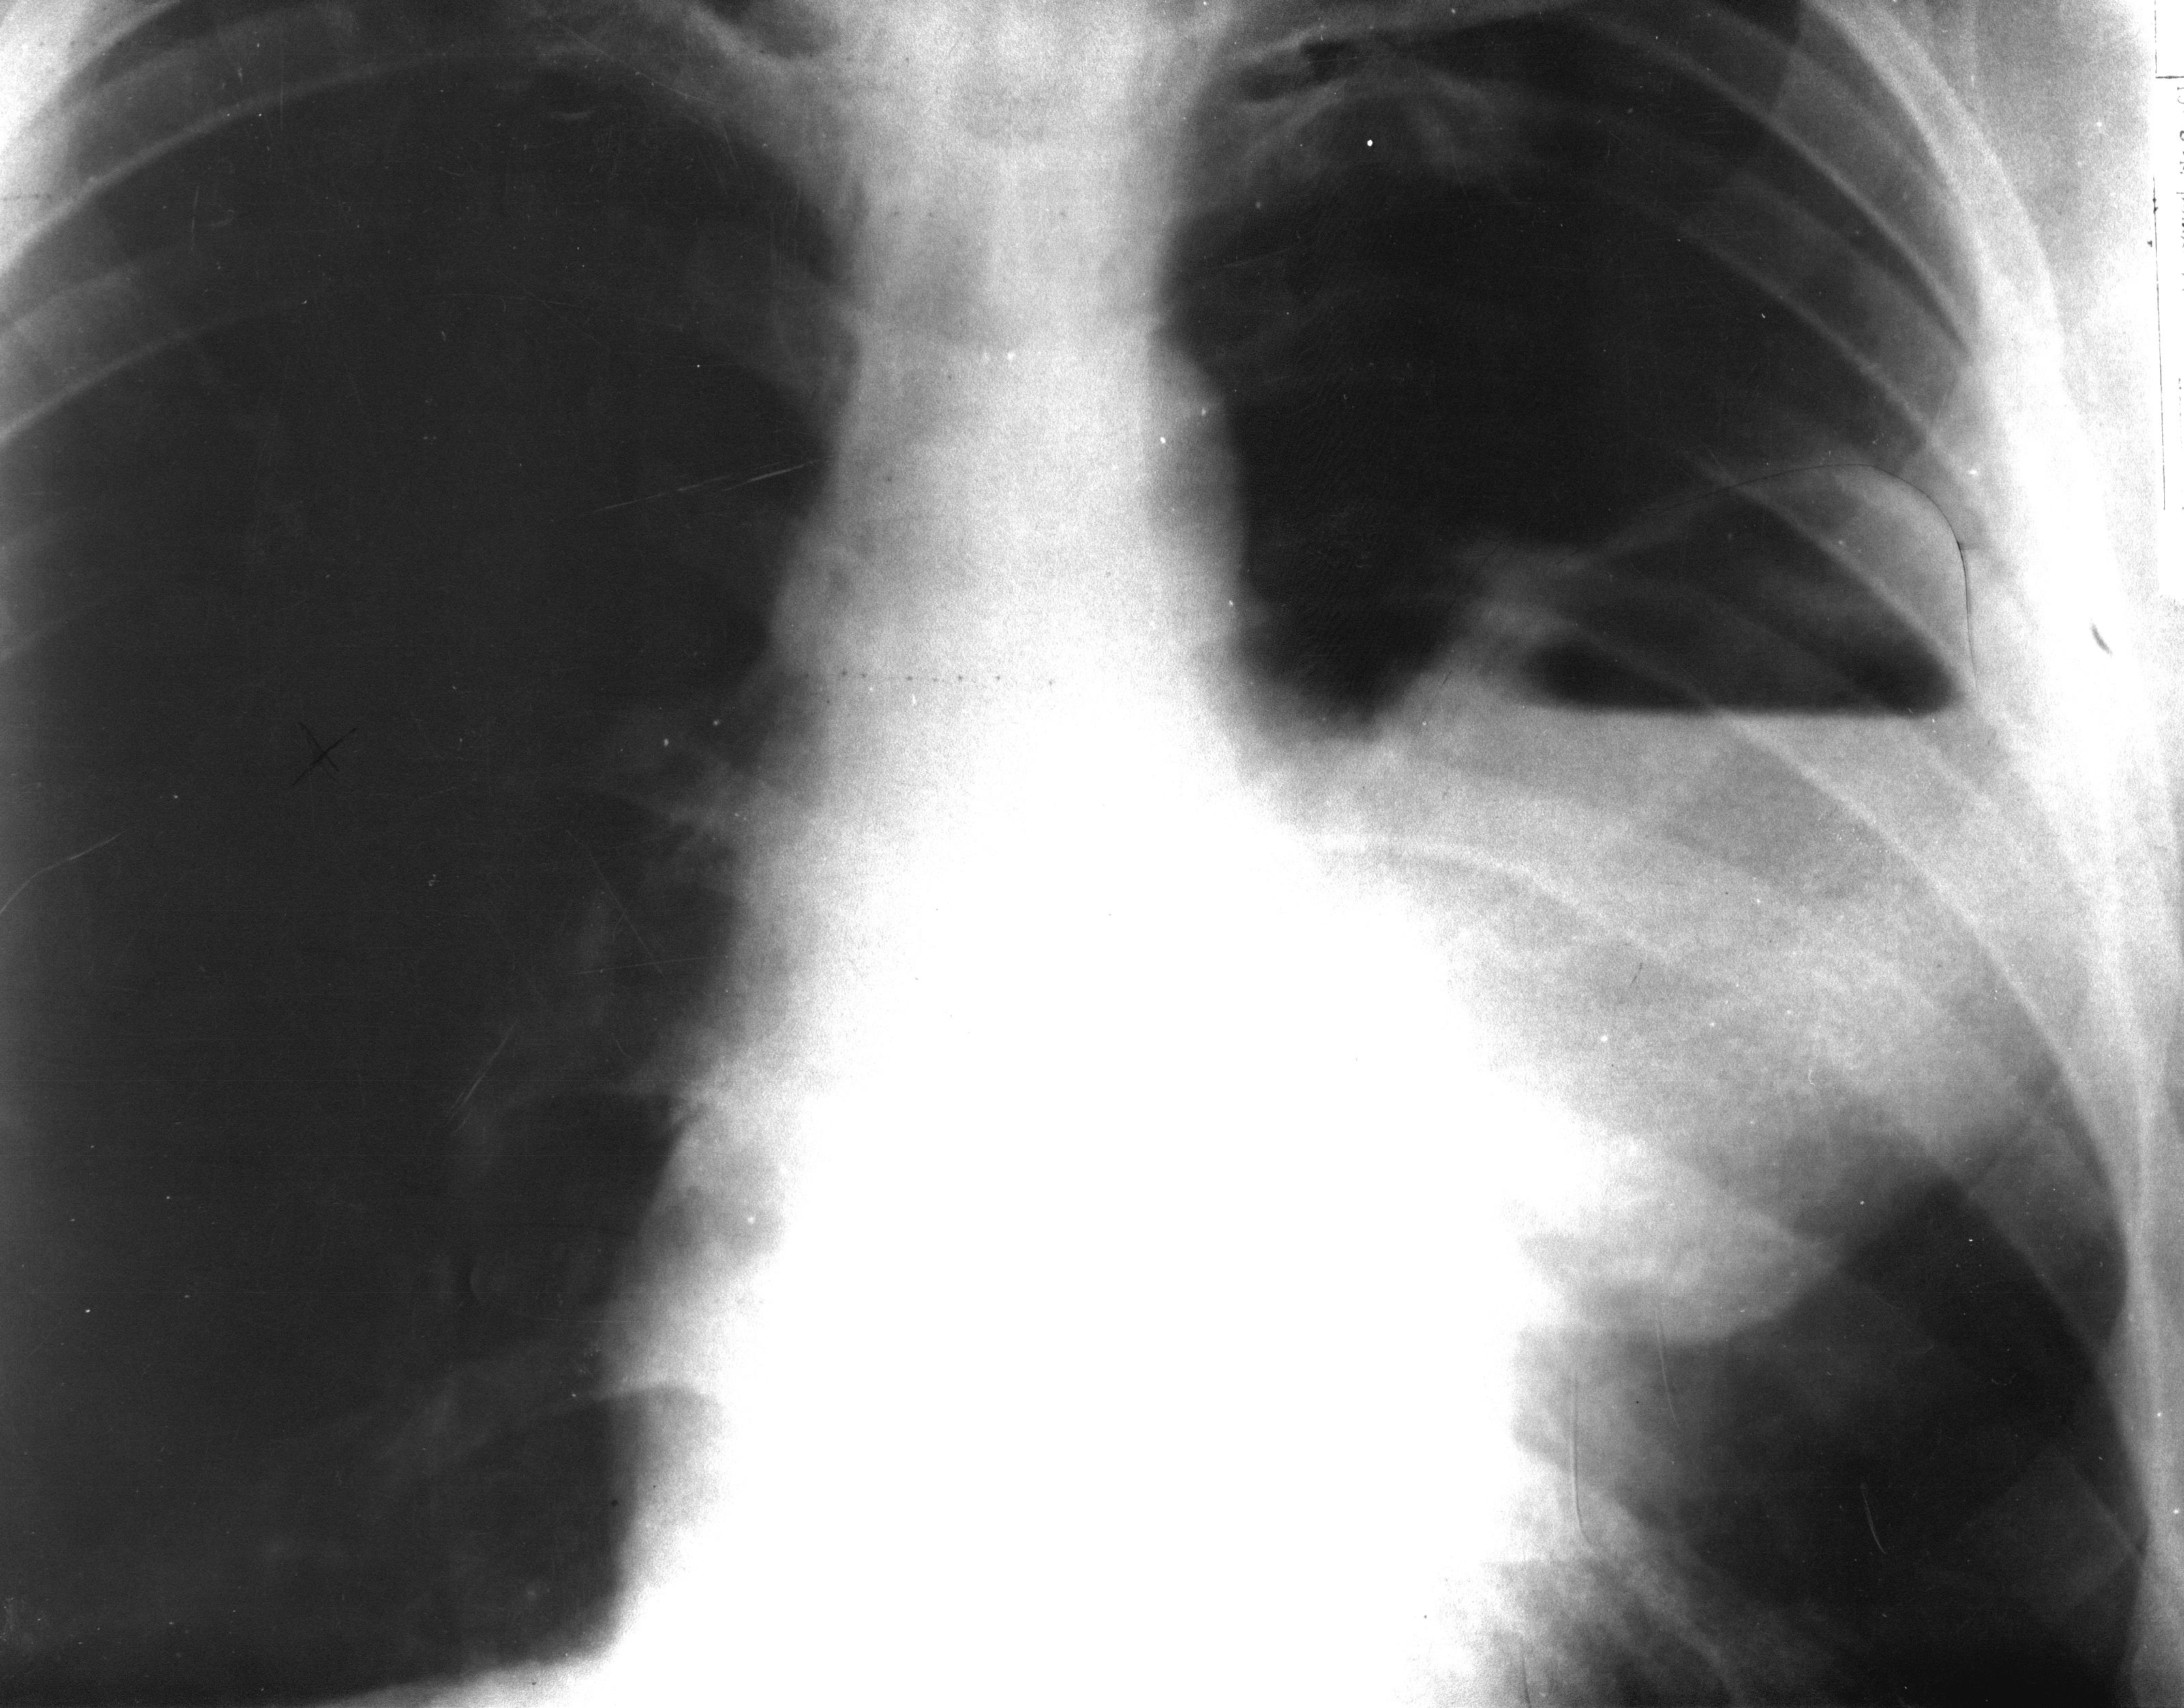

У больного в возрасте 50 лет после переохлаждения температура тела повысилась до 39,5°С, появились боли в груди слева, усиливающиеся при дыхании, отмечено отхождение скудной слизистой мокроты. Высокая температура наблюдалась в течение недели. Затем количество выделяемой мокроты с неприятным запахом увеличилось до 200 мл в сутки, общее состояние больного улучшилось, температура снизилась до нормы. При обследовании в левой подлопаточной области определялись укорочение перкуторного звука, ослабленное дыхание. Сделана рентгенограмма грудной клетки в прямой проекции.

Опишите рентгенограмму легких.

О каком заболевании следует думать? Поставьте предварительный диагноз.